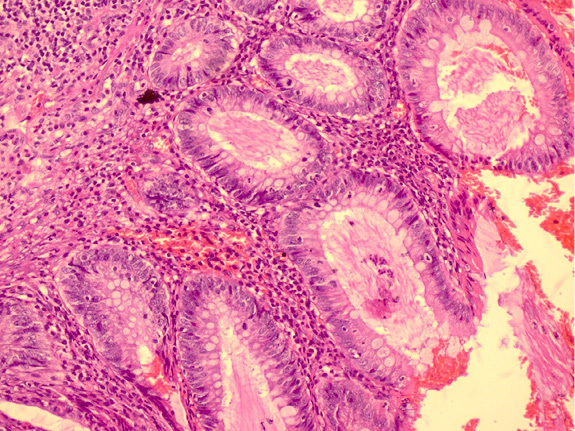

Figure 1. Bilaterally interstitial reticular densities and tram-tract appearance due to bronchiectasis in X-ray graph

In the systemic examination, bilaterally rales were present in lung auscultation. The peripheral pulses were normal. S1 and S2 were rhythmic, with no murmur, in normal sinus rhythm. In the laboratory, the neurological examination was normal. In X-ray chest graph, bilaterally tram-track linear opacities were observed [Figure 1]. These signs were interpreted as bronchiectasis due to CF. The patient had defences and rebound in the abdominal examination. WBC was 14,000×109/L. In the USG, the appendix was distended and no taken response to compression. He was operated on with a preliminary diagnosis of acute appendicitis. Unfortunately, since this rare diagnosis of the patient was not predicted, no images were obtained during the operation and sonographically.